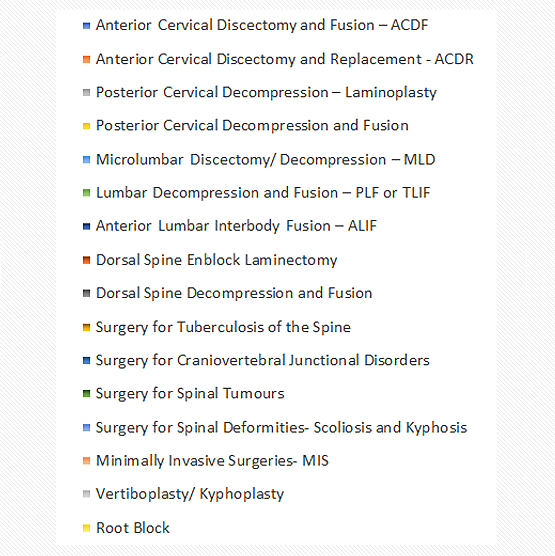

Some Common Operative Procedures